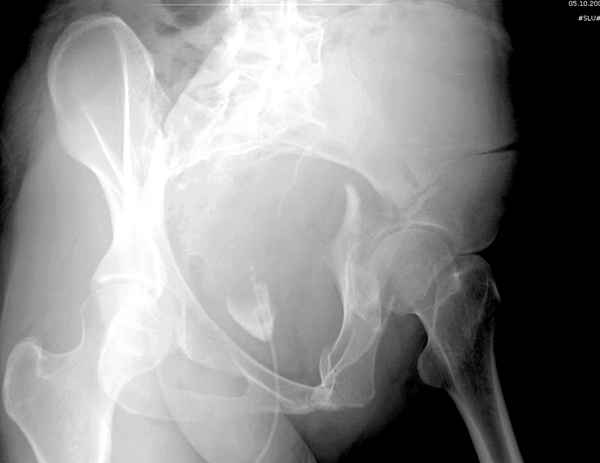

Поэтому хотелось бы дообследовать больного (разумеется включив стандартные проеции judet,и срезы показывающие сращение)

Пациент передвигается с помощью костылей с дозированной нагрузкой на правую ногу. При движении правой нижней конечностью ощущает щелчки. Болей в правом тазобедренном суставе в настоящее время нет. Вся правая нижняя конечность умеренно ротирована наружу.

С уважением Батал Шушания.

Хорошо бы на рентгенограммы взглянуть и побольше срезов по своду. С каким отломком головка контактирует и как ее состояние.

Дополнительные сканы